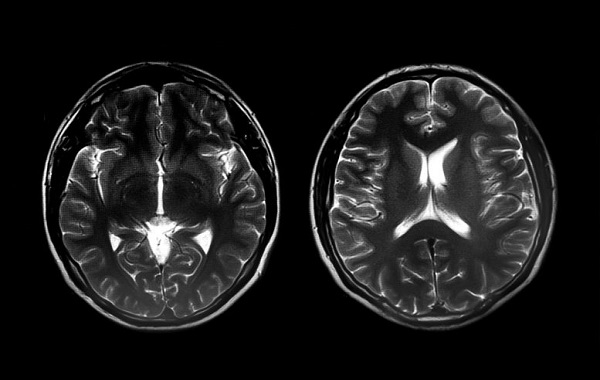

Brain organization differs between boys and girls with autism, according to a new study from the Stanford University School of Medicine.

The differences, identified by analyzing hundreds of brain scans with artificial intelligence techniques, were unique to autism and not found in typically developing boys and girls. The research helps explain why autism symptoms differ between the sexes and may pave the way for better diagnostics for girls, according to the scientists.

The study analyzed functional magnetic resonance imaging brain scans from 773 children with autism — 637 boys and 136 girls. Amassing enough data to include a sizeable number of girls in the study was challenging, Supekar said, noting that the small number of girls historically included in autism research has been a barrier to learning more about them. The research team relied on data collected at Stanford and on public databases containing brain scans from research sites around the world.

Using 678 of the brain scans from children with autism, the researchers developed an algorithm that could distinguish between boys and girls with 86% accuracy. When they verified the algorithm on the remaining 95 brain scans from children with autism, it maintained the same accuracy at distinguishing boys from girls.

The scientists also tested the algorithm on 976 brain scans from typically developing boys and girls. The algorithm could not distinguish among them, confirming that the sex differences the scientists found were unique to autism.

Among children with autism, girls had different patterns of connectivity than boys did in several brain centers, including motor, language and visuospatial attention systems. Differences in a group of motor areas — including the primary motor cortex, supplementary motor area, parietal and lateral occipital cortex, and middle and superior temporal gyri — were the largest between sexes. Among girls with autism, the differences in motor centers were linked to the severity of their motor symptoms, meaning girls whose brain patterns were most similar to boys with autism tended to have the most pronounced motor symptoms.